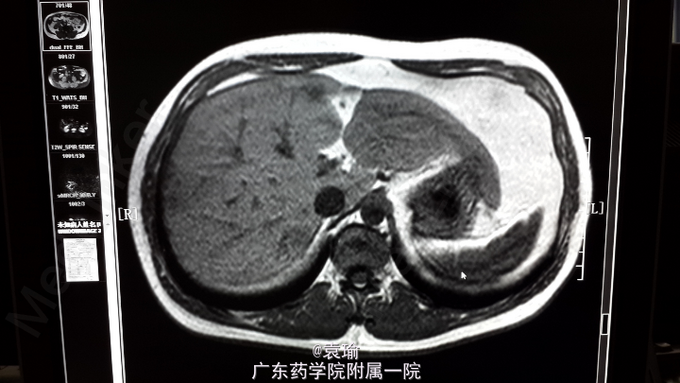

查体:T 36.5℃,P82次/分,R20次/分,BP 105/73mmhg, 巩膜轻度黄染,全身 皮肤无黄染,无贫血貌,未见肝掌、蜘蛛痣,浅表淋巴结未扪及肿大。心、肺查体无明显异常。腹平坦,腹肌软,右上腹轻压痛,无反跳痛,全腹未扪及明显包块,肝、脾肋下未扪及,墨菲氏征阴性,麦氏点无压痛,肝浊音界存在,肝肾区无叩击痛,腹部移动性浊音阴性,肠鸣音活跃。 辅助检查:多次血常规检查见嗜酸性粒细胞计数及比例增高(见附图),肝功能检查异常(见附图),超敏C反应蛋白6.200mg/L,降钙素原0.076ng/ml,余大、小便常规正常,多次大便找虫卵阴性,肾功能、凝血功能、血脂均正常,肿瘤指标(AFP、CEA、Ca-199、CA-125、CA-724、CA-153)均正常,胃镜检查示非萎缩性胃炎轻度,多点活检未见明显嗜酸性粒细胞浸润。腹部MR+MRCP:肝内多发异常信号影,考虑感染性病变,注意寄生虫感染可能,MRCP未见异常。